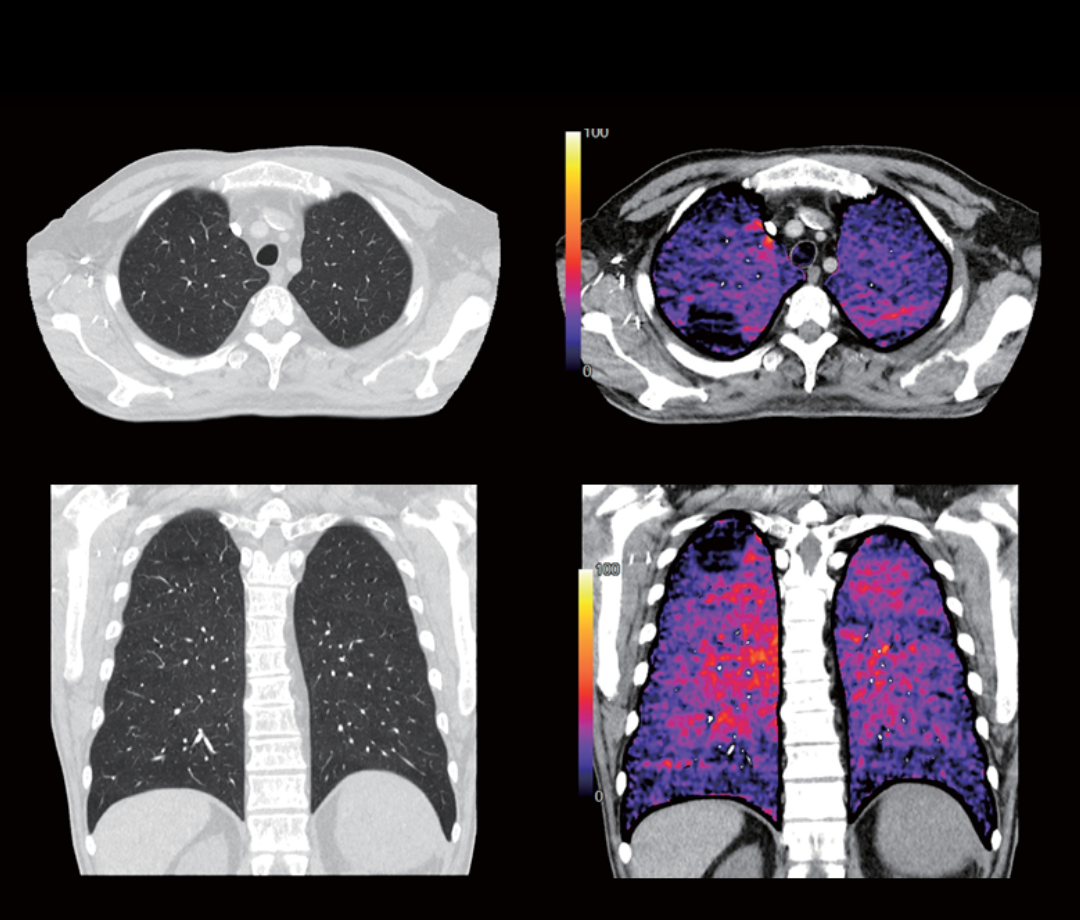

• КТ-ангіографія легеневих артерій зі застосуванням йодних карт від Canon Medical

29.09.2025